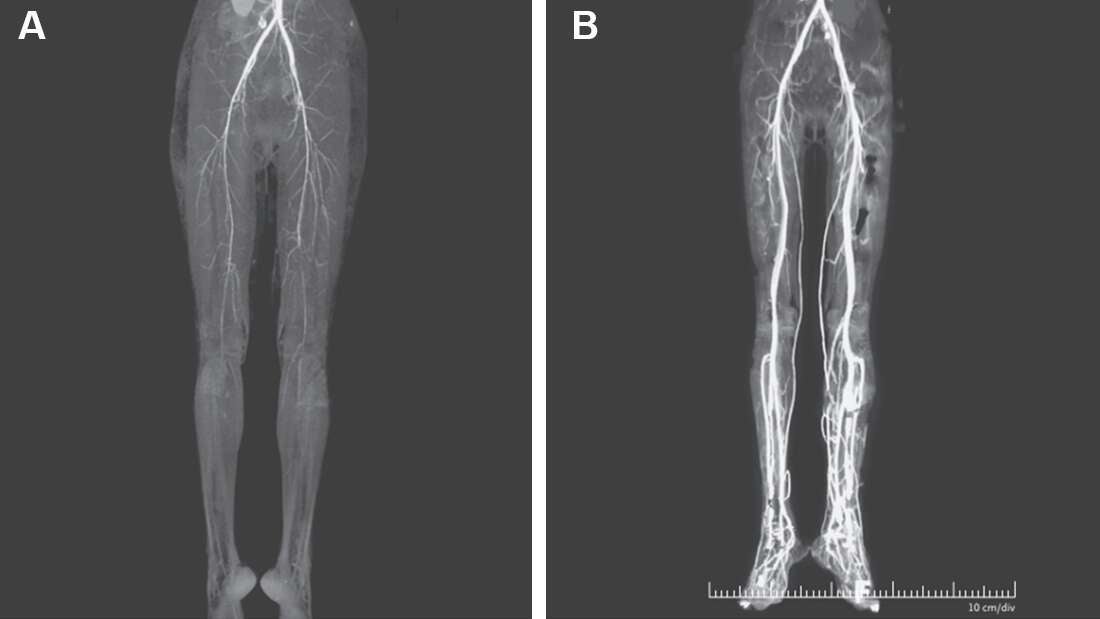

Posteriormente, una tomografía computarizada (TC) mostró “estrechamiento de las arterias”. Se le dio un anticoagulante (heparina), y el dolor en las piernas mejoró y se calentaron a medida que aumentaba el flujo sanguíneo. Desafortunadamente, uno de sus dedos tuvo que amputarse debido a la gangrena.

En el trabajo publicado los doctores concluyen que dos semanas después del tratamiento y al dejar de tomar el medicamento, la paciente mejoró el flujo sanguíneo en sus piernas. [The New England Journal of Medicine vía IFLScience]